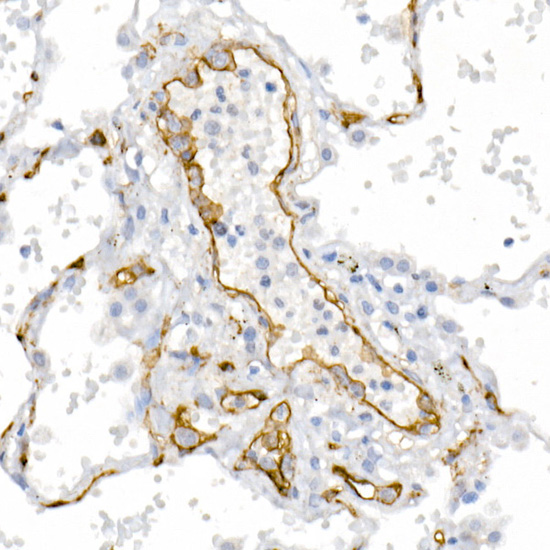

Immunohistochemistry of paraffin-embedded human lung using CD146/MCAM Rabbit pAb.